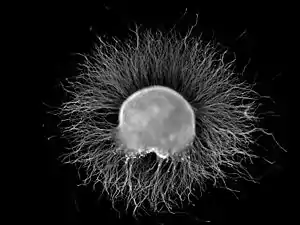

| Ganglion | |

![]() Micrograph of a ganglion. H&E stain. | |